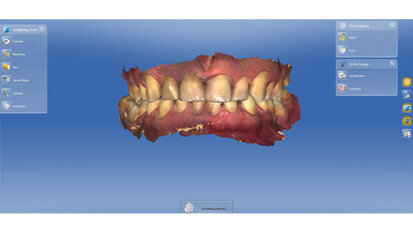

Rehabilitace Straumann